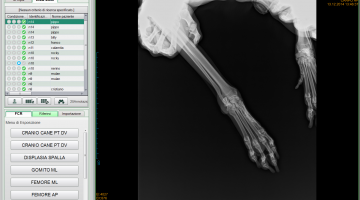

Attualmente la nostra struttura è munita di un apparecchio radiologico digitale indiretto Fuji. (Nella photogallery in basso). I vantaggi di questa tecnologia rispetto alla radiologia “analogica “ tradizionale sono molteplici. Primo fra tutti la qualità dell’immagine e la possibilità di ingrandire i particolari, correggere i contrasti, visualizzarla in negativo, ma anche misurare con precisione i dettagli. Poi la notevole riduzione dei tempi dello studio radiografico che in campo veterinario significa anche la riduzione dei tempi di anestesia del paziente con beneficio per la sua salute. Le lastre digitali non inquinano l’ambiente. Sono dei files che possono essere trasmessi per posta elettronica, masterizzati su cd o pennette di memoria da mettere nella cartella clinica da consegnare al proprietario del paziente e, nel caso della nostra struttura allegati in rete e nella scheda clinica dell’animale.